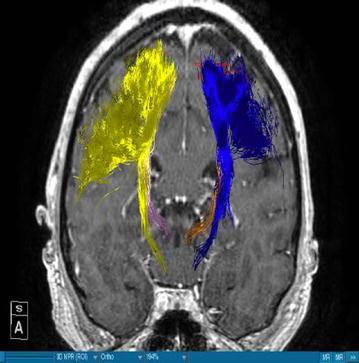

We were able to successfully portray these white matter tracts in all patients. We visualized the medial and lateral parts of the corticospinal tract by using a region of interest which covered the whole motor cortex. Furthermore we segmented the motor cortex. The fibers ran from this area of the brain through the internal capsule and they could be followed until their entry in the brainstem. The dentatorubrothalamic tract was smaller than the corticospinal tract. It was situated medio-posteriorly of the corticospinal tract. After decussation to the contralateral red nucleus it was localised next to the midline when it entered the motor cortex. From the thalamus on, it proceeds medially and posteriorly of the corticospinal tract further to the motor cortex. Depiction of the whole tract is essential for the differentiation of the dentatorubrothalamic tract with the corticospinal tract.

The depiction of the dentatorubrothalamic tract might be useful for neurosurgeons when deep brain stimulation is planned. Knowing its relation to other white matter tracts can help physicians like neurosurgeons or neurologists avoid side effects and deal with patients with DBS. The position of the electrode might be crucial for a satisfactory outcome.